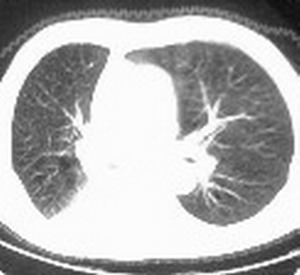

标题: CT6943:[讨论]胸部,M/67Y,体检发现。 [打印本页]

标题: CT6943:[讨论]胸部,M/67Y,体检发现。

ct值约12hu。